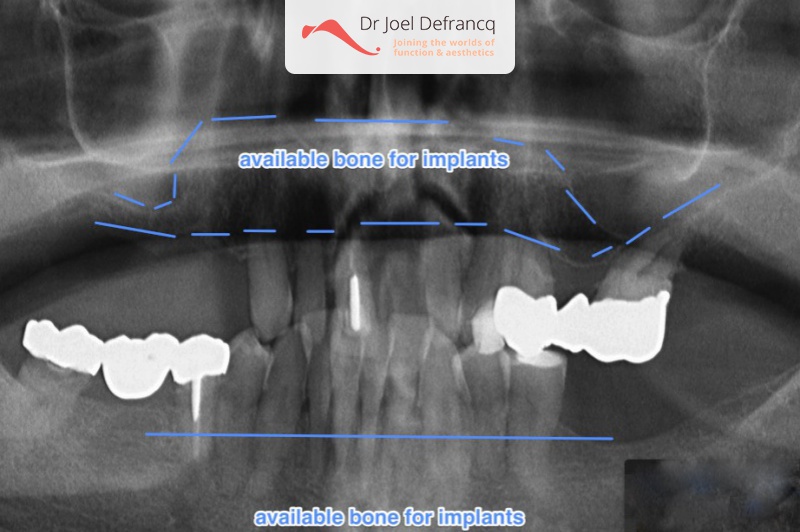

- Falende tanden. Immediate belasting op de implantaten (één week).

- Vaste tanden op implantaten (bovenkaak)

- Vaste tanden op implantaten (onderkaak)